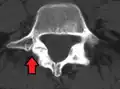

Computed Tomography (CT)

Computed tomography can be helpful in evaluating bony vertebral abnormalities, such as fractures.[33] This can be helpful in determining if the fracture is a new, old, and/or progressing fracture.[33] CT use in spondylolisthesis evaluation is controversial due to high radiation exposure.[34]